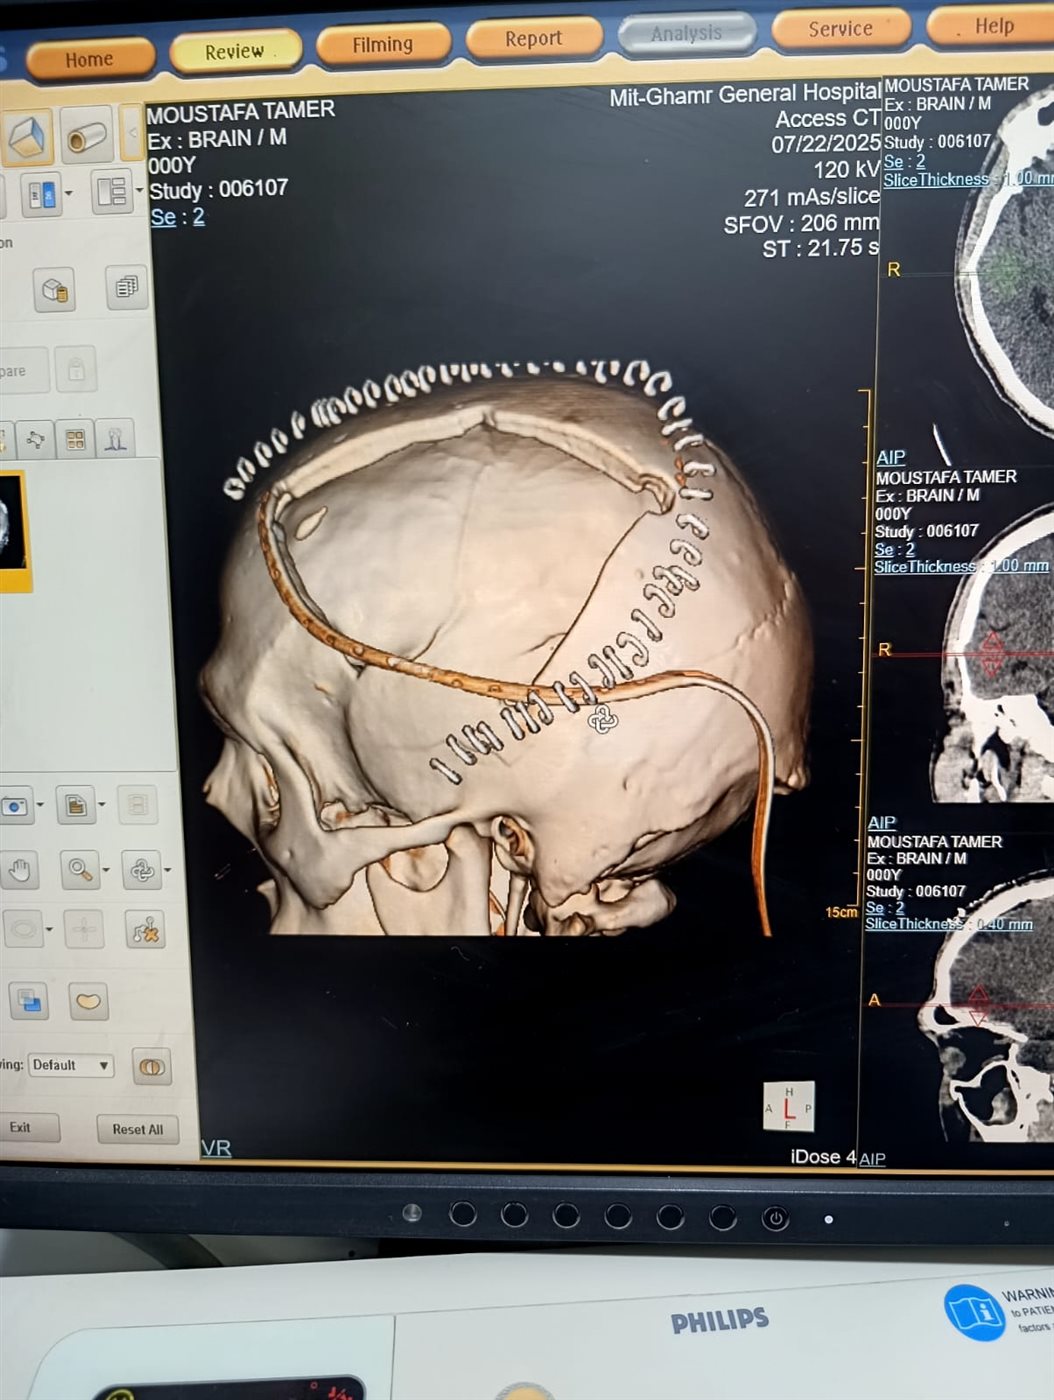

جراحة دقيقة لتفريغ التجمع الدموي وإزالة رقعة كبيرة من عظام الجمجمة

من جهته، أشار الدكتور السيد فاروق، وكيل المديرية للطب العلاجي، إلى أن الفريق الطبي أجرى جراحة دقيقة لتفريغ التجمع الدموي وإزالة رقعة كبيرة من عظام الجمجمة لتخفيف الضغط الدماغي، وهي تقنية معقدة يتم خلالها زراعة العظام في جدار البطن الأمامي لحفظها حيويًا حتى يعاد تركيبها لاحقًا بعد تحسن الحالة.

أجريت الجراحة تحت إشراف الدكتور أحمد محمد سليمان، مدير مستشفى ميت غمر العام، وشارك فيها الدكتور شريف سليمان، استشاري جراحة المخ والأعصاب والعمود الفقري، وضم الفريق الدكتور محمد البربري والدكتور محمد نادر من فريق التخدير، بمشاركة متميزة من طاقم التمريض.